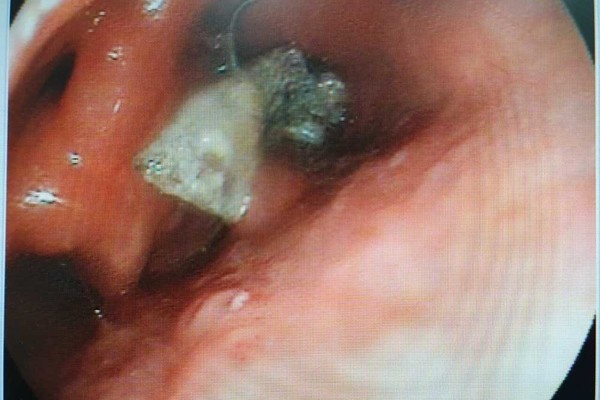

| Hình ảnh nội sôi 4 chiếc răng giả rơi vào trong dạ dày bệnh nhân |